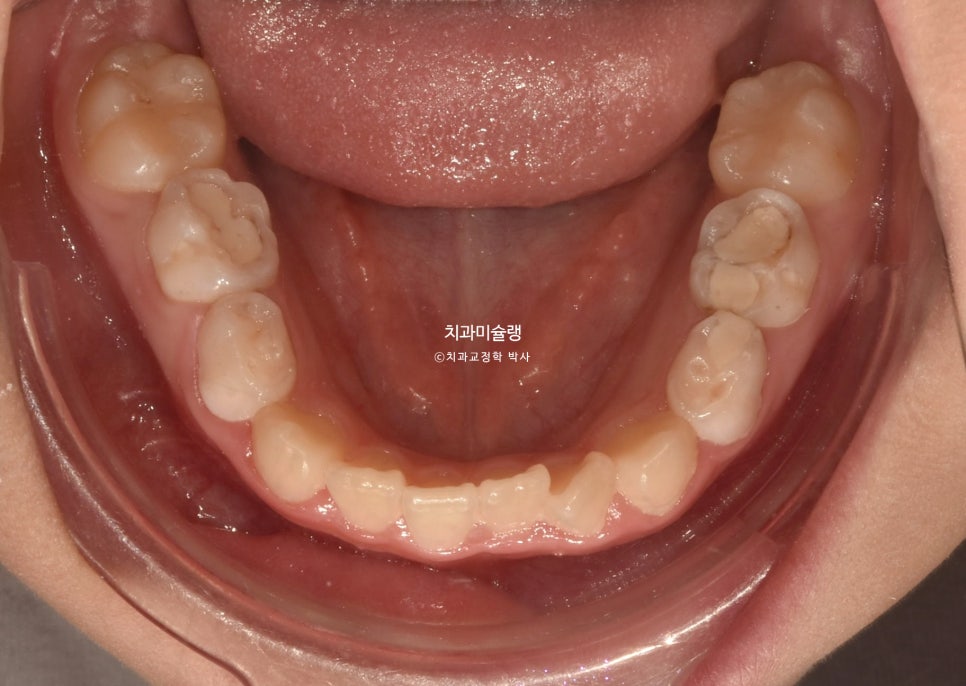

초진 시 상태 및 진단

24년 6월, 교정치료를 위해 내원한 만 10세 어린이 입니다.

송곳니 덧니와 개방교합이 보입니다.

위 앞니가 아래 앞니를 덮지 못하고 아래 앞니가 더 앞으로 나가있는 반대교합 입니다.